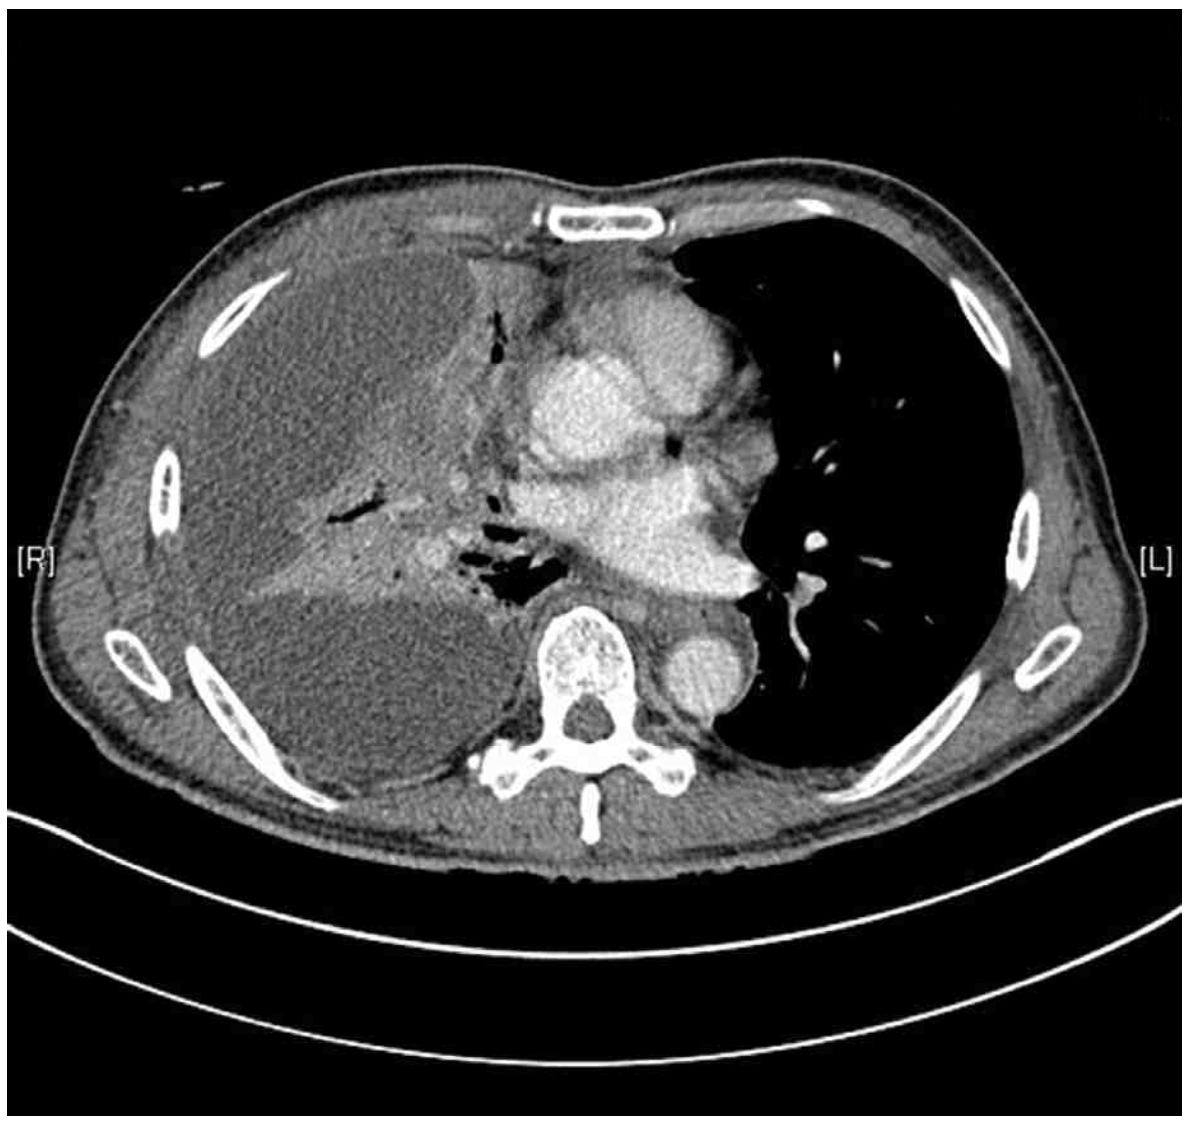

69세 남자가 1주 전부터 열이 나고 오한이 들어 병원에 왔다. 1일 전부터 가슴통증이 심해지고 숨이 찼다고 한다. 당뇨병으로 치료 중이고 비흡연자이다. 혈압 136/80 mmHg, 맥박 102회/분, 호흡 24회/분, 체온 38.6°C이다. 오른쪽 가슴에서 호흡음이 감소되어 들린다. 가슴 X선사진과 가슴 컴퓨터단층촬영 사진이다. 검사 결과는 다음과 같다. 검사는?

CXR: Rt. pleural effusion

CT: Rt. pleural effusion, loculated

• CXR상 우측 흉강의 pleural effusion을 관찰할 수 있으며 chest CT에서도 해당 부위의 loculated pleural effusion을 확인할 수 있다. 현재 발열, 빈맥, 빈호흡 및 CRP elevation, neutrophil-dominant leukocytosis 등으로 보아 세균성 감염이 원인으로 추정되며, 환자가 당뇨병으로 치료 중이라는 점에서 감염에 취약한 상태일 가능성을 배제할 수 없다.

• CXR 및 chest CT를 통해 흉수의 존재를 확인하였으므로 진단적 흉막천자를 통해 그 원인을 감별하여야 한다.